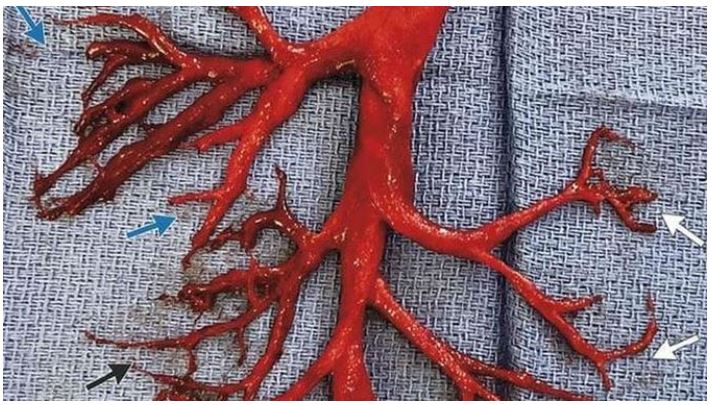

Embalmers Are Making Shocking Discoveries in the Blood of the Dead

It sounds like a bad horror movie script from the 1960s, but it isn’t. The Epoch Times is repo